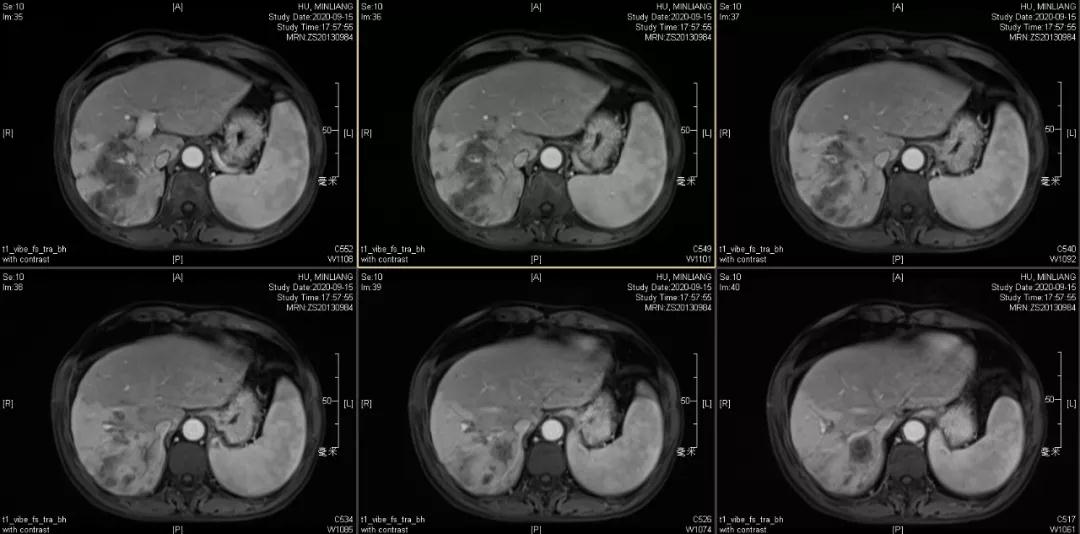

肿瘤学评估(用药后2个月对比6个月):肝内主瘤明显缩小,动脉期强化降低;子灶消失;门脉右支癌栓明显缩小坏死;肺转移灶缩小,大部分消失。

2020-09-15

2021-01-25

Δ治疗过程中病灶影像学变化